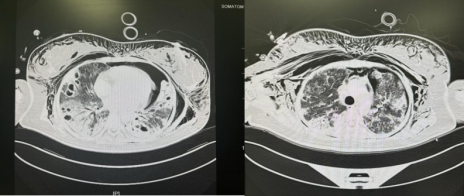

入院后,医护人员立即给予小丹积极救治并行相关检查以便进一步了解情况,通过影像学检查医生发现小丹颌面部、颈部、胸腹壁、腰背部、双侧上臂弥漫性皮下气肿及纵隔气肿;左侧气胸,肺压缩约40%;双肺散在渗出伴多发空洞影及双肺脓肿,肺功能损害严重,呼吸困难,血氧饱和度急剧下降,气管插管并呼吸机支持下(氧浓度100%)血氧极差,氧合指数仅有60mmHg(正常的氧合指数约在400-500mmHg),且出现了严重的血流动力学不稳定,难以进行俯卧位行肺复张治疗。与此同时,小丹再次出现心脏骤停,这突如其来的病情恶化打乱了重症医学科团队原先拟定的诊疗计划,医护人员不得不进行调整治疗方案。

随着时间的流逝,小丹的氧合逐渐改善,ECMO流量在逐渐下调,当流量调整至0时,仅在呼吸机的支持下血氧就能达到95%-100%,氧合指数能达到250以上。经科室讨论,小丹已达到撤机标准,重症医学科团队立即组织医疗小组带小丹复查肺部相关影像,从CT上看小丹的肺部得到了改善。2024年9月29日,在重症医护人员的配合下,小丹顺利撤机,这也是ECMO支持成功的最后一步,但接下来的治疗对医护人员来说又是一个新的挑战。